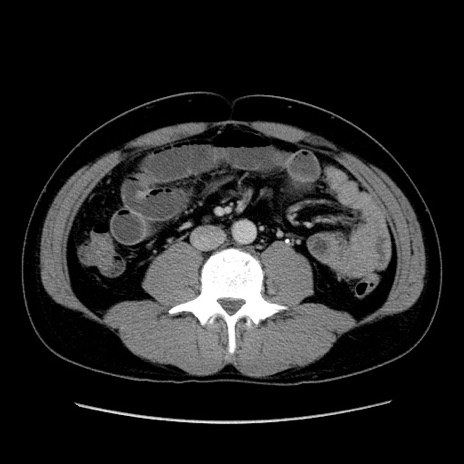

症例4(横断像)

【症例】30歳代男性

【主訴】腹痛、嘔吐

【現病歴】昨晩から突然の腹痛あり、その後嘔吐、軟便も出現。腹痛が改善しないため救急搬送となる。2日前にしめ鯖の食事歴あり。

【身体所見】意識清明、苦悶様、BP 135/90mmHg、BT 35.7℃、腹部:平坦、やや硬、心窩部〜臍部に自発痛、圧痛あり、筋性防御+、反跳痛-

【データ】WBC 8100、CRP 0.57